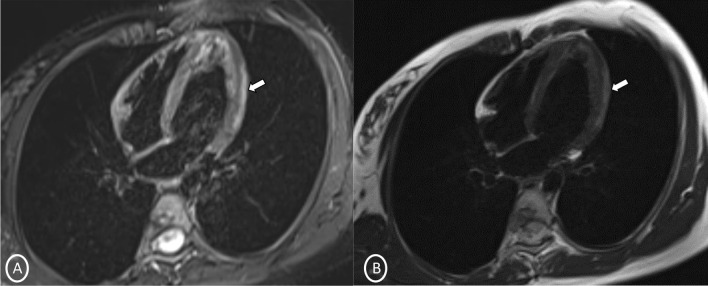

A 19-year-old female had presented to our Emergency Department, complaining of sudden severe chest and epigastric pain since 1 day, which was associated with sweating. The pain was radiating to neck and left arm. The pain did not relieve on rest but subsided on medications. Similar episodes were also reported in the past few days, however, with less severity. The patient confirmed to not having shortness of breath, palpitation, syncope, dizziness, nausea, emesis, fever, or cough. There was no history of any previous cardiac ailment/surgery/other identifiable cardiovascular risk factors or any other history of infection. There is no evidence to suggest chest wall trauma. There is no history of comorbidities or any history of smoking. There is no significant family history or any similar past history. Upon admission, patient was conscious, alert with heart rate of 86 bpm, blood pressure measuring 110/60 mm Hg, 97% oxygen saturation at room air, temperature of 36.4 °C, and respiration rate of 15 breaths/min. The cardiac biomarker troponin T levels were extremely raised, measuring 50,000 pg/ml, and CK-MB was raised, measuring 111U/Lt. Laboratory findings showed that inflammation markers were normal, C-reactive protein (5.8.0 mg/L) and D-dimer (94 ng/mL). Other laboratory findings such as lipid profile, complete blood count, electrolytes, fasting blood glucose, HBA1c, and renal and liver function tests were normal. Cardiac auscultation showed normal S1, S2 without murmurs or pericardial rub and any sign of heart failure. Initial ECG revealed ST segment elevation in the leads I, aVL, V4, V5, and V6 leads, normal sinus rhythm (60 beats per min) without any other abnormalities (Fig. 1), which was resolved by day 3. Arrhythmias were not found during continuous cardiac monitoring. Echocardiogram showcased an ejection fraction of the left ventricle to be 60%, whereas the echocardiographic metrics were not very significant. Patient was then treated as ACS with a salicylate-based nonsteroidal anti-inflammatory drug (NSAID), anticoagulants, and anti-thrombolytics. CMR was done on 3 T MRI machine with acquisition including T2/STIR Dark blood four-chamber long axis; CINE images in short axis, long axis, RVOT, and LVOT; and early dynamic gadolinium enhancement images and delayed gadolinium enhancement in PSIR images. T2/STIR Dark blood sequences showed T2 hyperintensity in the subepicardial region along left lateral wall (Fig. 2A, B). There was associated mild global hypokinesia with mildly reduced ejection fraction/systolic function (Fig. 3A, B). Patchy delayed gadolinium enhancement of intramural, subepicardial as all tans-mural enhancement with non-involvement of the subendocardium (suggesting a non-ischemic pattern) in multiple segments of cardiac basal (Fig. 4A, B), mid cavity (Fig. 5A, B), and apical cavity—with predominant involvement of lateral (Fig. 6A, B) and inferior wall segments in the basal cavity. There were no signs of infarction of myocardium; therefore, the patient was diagnosed with acute myocarditis (based on Lake Louise Criteria for Acute Myocarditis). Further, viral and autoimmune workups results were found to be negative. It included hepatitis (B, C), human immunodeficiency virus, Coxsackie virus, COVID-19, cytomegalovirus, Epstein–Barr virus (EBV), and Parvovirus B-19. On further analysis and detailed relevant history workup, the patient admitted to using cannabis for the past 1 year with last exposure being 3 days before admission. On the basis of detailed clinical history, findings on CMR with other negative viral markers, and possible etiological factors, a final diagnosis of myocarditis presumed secondary to marijuana/cannabis toxin abuse was made. Patient was released from the hospital on the seventh day with advised conservative treatment. The patient was counseled to abstain completely from cannabis or related drugs. Patient was advised to repeat a CMR control, three months later. A 3–4-month restriction on high-intensity activity was also given to the patient following discharge.